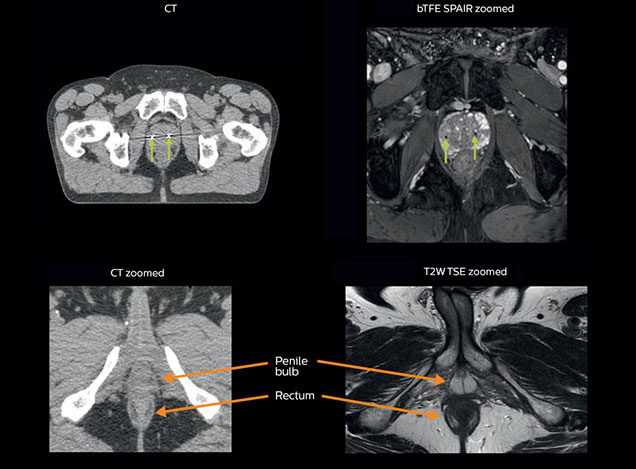

Visualizing critical structures with MRI before prostate radiation therapy

A 63-year-old patient with prostate cancer, cT3bNxM, Gleason 7, underwent MRI on Ingenia 3.0T MR-RT before radiation therapy.

Intraprostatic lesions are visible on the bTFE MR image, but not on the CT image. MRI shows excellent soft-tissue contrast for the visualization of critical structures like the rectum and penile bulb.

Fiducial markers (green arrows) are used in registration of MR images to CT, to transfer the MR-based delineations onto the CT image dataset.